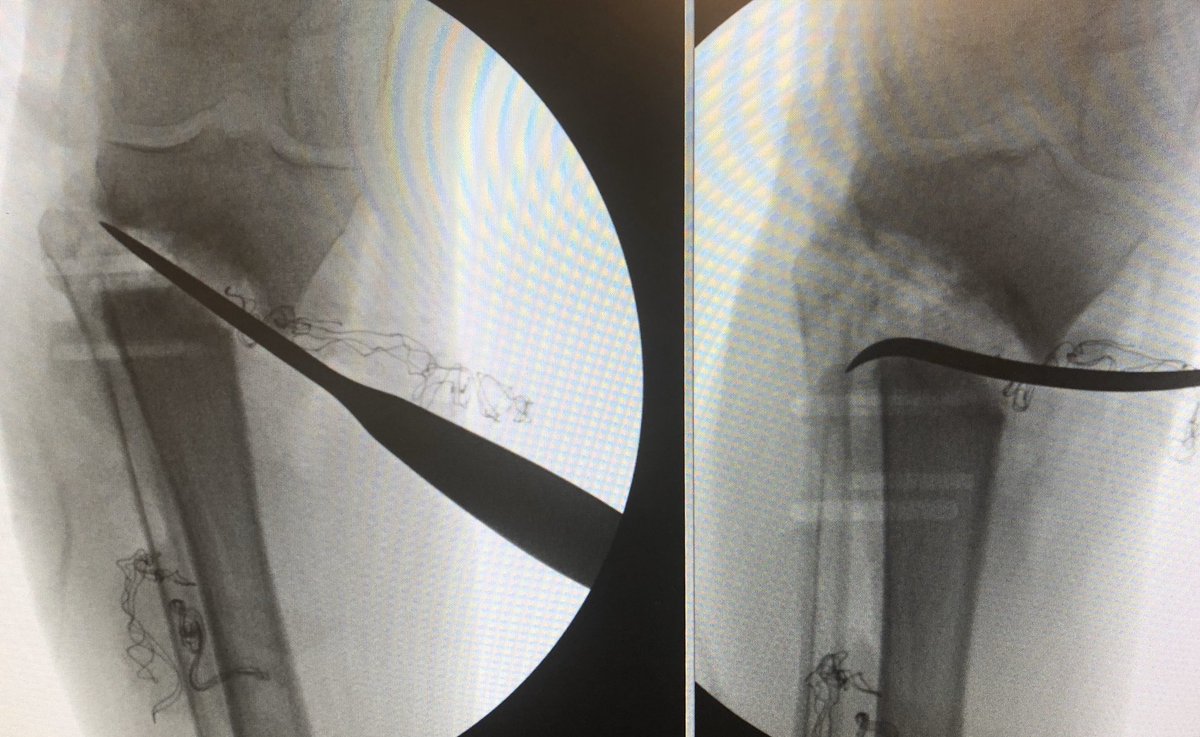

[6/9] Unlike my usual approach to do medial side first, here I fixed the lateral side, hopeful that anatomic fixation would help me obtain length of the posterior portion of the medial mal fracture via the PITFL (posterior portion of syndesmosis). It probably didn’t matter much.

[7/9] Here, you go where money is—posteromedial. As long as you understand anatomy and are careful, you can avoid or retract neurovascular bundle. This spike was behind tib posterior; I used K wire to confirm before I cut periosteum. Remember: “Tom Dick (And Very Nervous) Harry!”

[8/9] I was able to see both spikes and confirm they were part of same fragment. I reduced main one and held it with screws closer to joint (cancellous lag in metaphyseal bone since can’t be bicortical in this direction), then 2.4 buttress plate to counteract upward shear forces.

[9/9] Final images. It doesn’t take huge or expensive implants to get what you want— 1/3 tubular for fibula and tiny cute plate as the buttress (with no distal screws because it doesn’t need them to counter shear force).